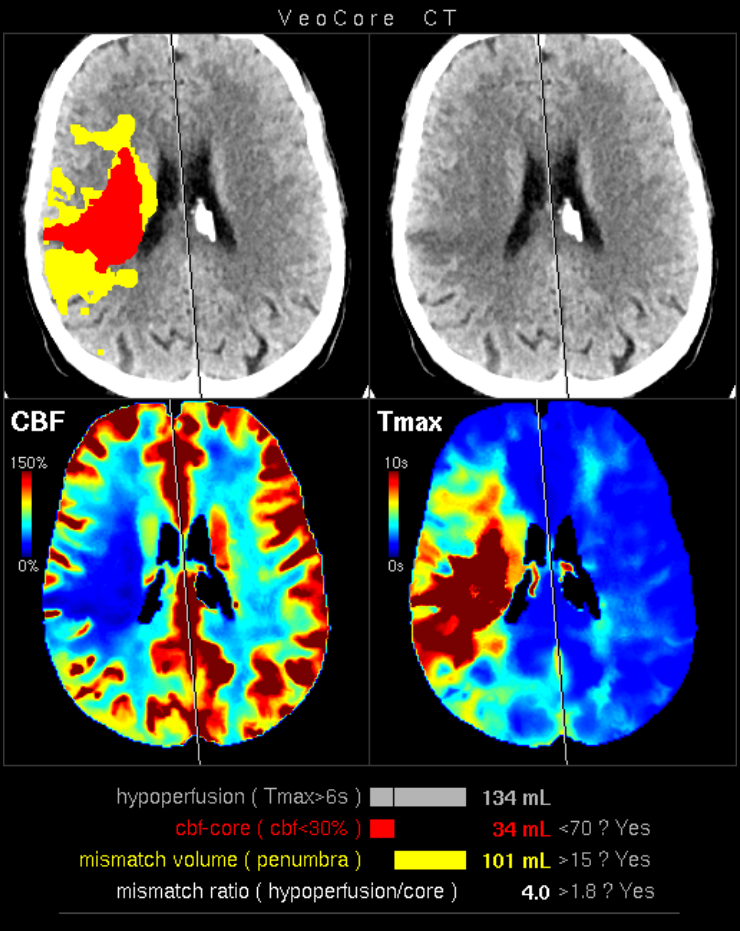

Des Weiteren ist mRay in der Lage eine Verarbeitung von Bildern durchzuführen und so Veränderungen bzw. Anomalien in Geweben zu finden, zu visualisieren und zu quantifizieren. Das Bildverarbeitungsmodul mRay VEOcore kann verwendet werden, um Bilder des Gehirns von Bildgebungsmodalitäten wie CT, Perfusions-CT oder MRT mit diffusionsgewichteter Auswertung (DWI) zu prozessieren. Als Ergebnis werden Kontrastveränderungen über die Zeit als farbige Perfusionskarten angezeigt, dies beinhaltet auch flussbasierte Parameter und Gewebeblutvolumen Berechnungen.

Die Perfusionsanalyse von Aufnahmen des Gehirns ermöglicht die Darstellung und Quantifizierung von minderdurchblutetem Gewebe (Penumbra), nicht-durchblutetem Gewebe (Kerngewebe) und dem Mismatch-Ratio zwischen den beiden Werten. Die berechneten Werte können der Unterstützung bei einer Entscheidungsfindung dienen, die auf der Beurteilung des Ausmaßes der Schädigung von Geweben basiert.